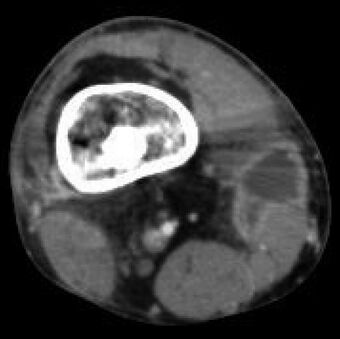

Osteomyelitis

Brodie abscess